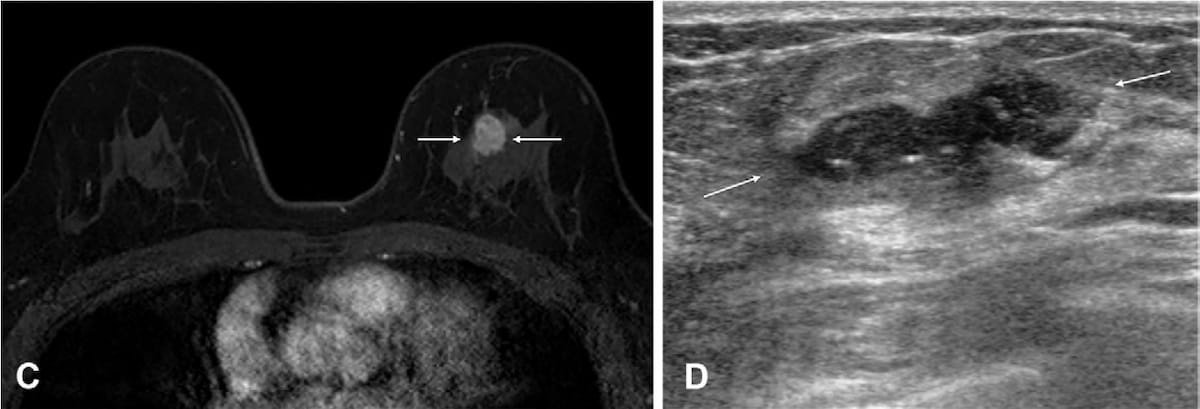

Here one can see an 18 mm irregular heterogeneous enhancing mass in the left breast on the contrast-enhanced, T1-weighted MRI (left) for a 55-year-old woman. The mass was subsequently confirmed as a human epidermal growth factor receptor 2 (HER-2)-positive invasive ductal carcinoma after breast-conserving surgery. In the surveillance ultrasound scan, obtained 11 months later, one can see a new 25 mm irregular hypoechoic mass, which was subsequently confirmed as a recurrence of invasive, HER-2 positive ductal carcinoma. (Images courtesy of Radiology.)